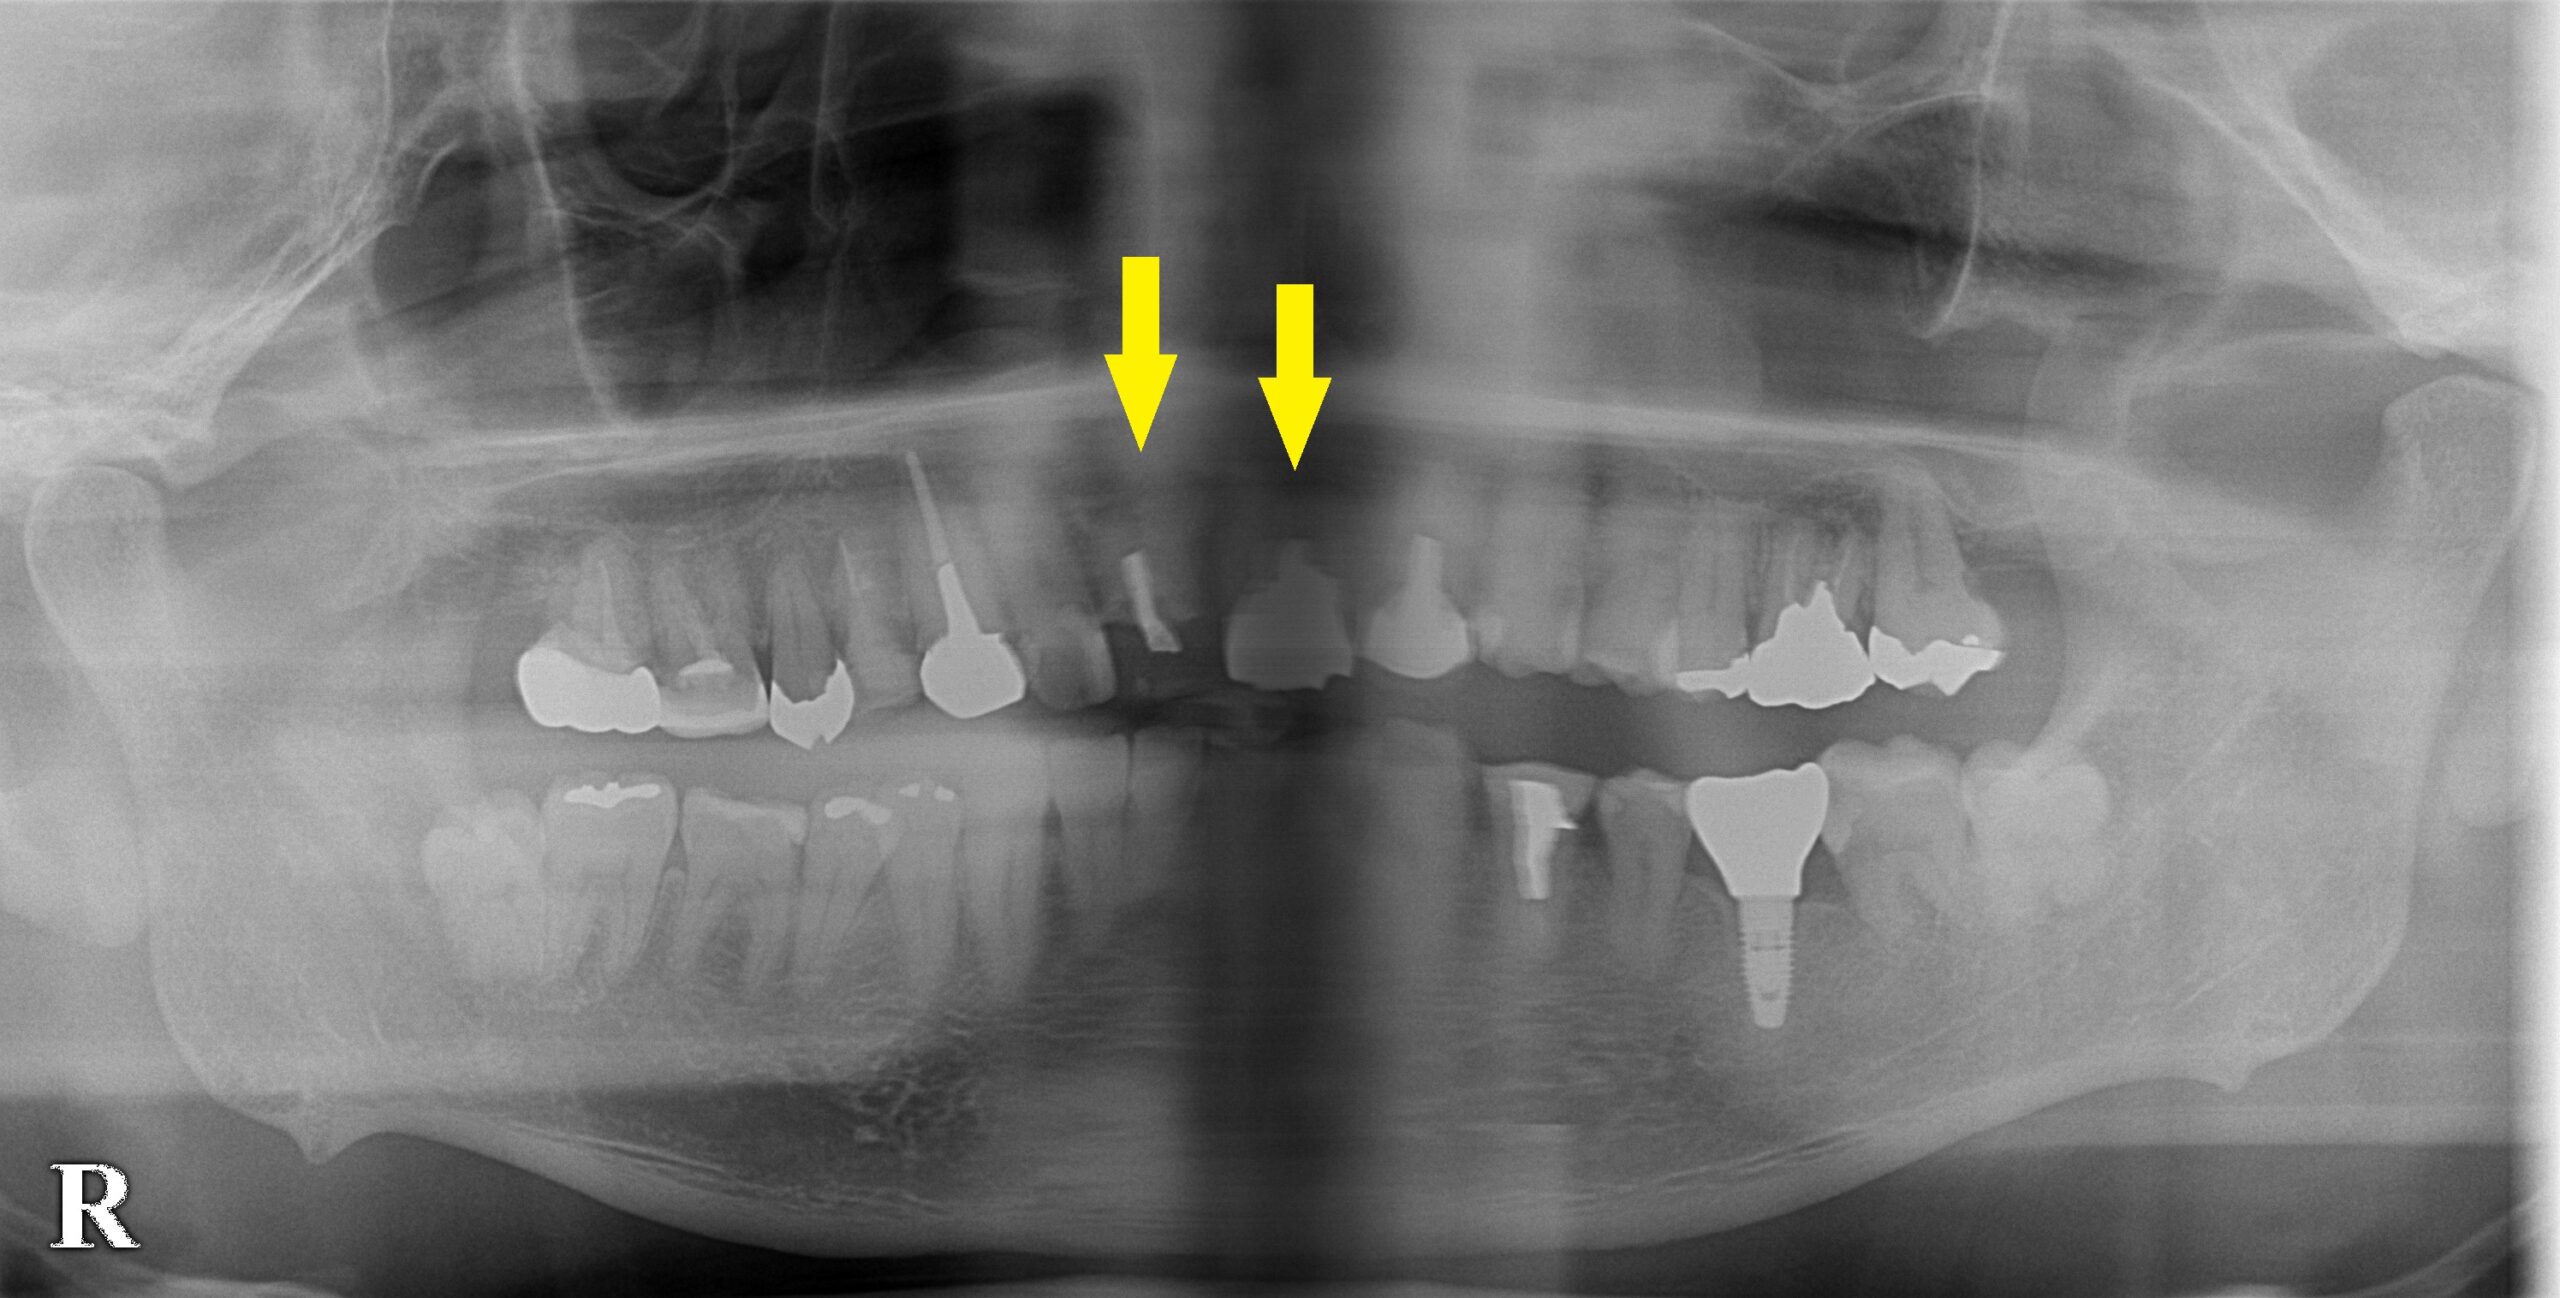

レントゲン写真、CTを撮ってみると、下の写真、中段のように歯根の先まで、骨が吸収されてしまっていました。